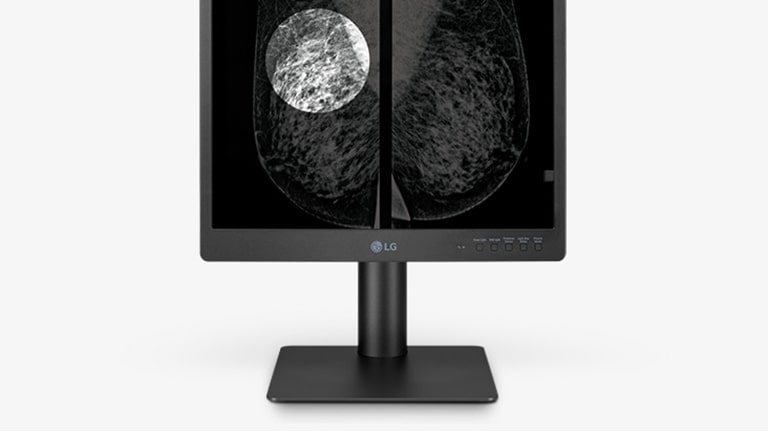

Multi-resolution mode

Set the resolution mode to fit your needs

The various resolution modes (5/3/2MP) of the 21HQ613D allow users to customise their resolution to better fit their respective needs.

*All images are shown for illustrative purposes only and may vary from the actual product/usage.